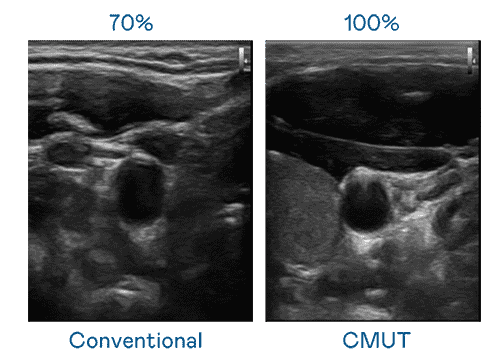

CMUT 技术是一种用电容式微机电元件来产生超音波讯号的技术。。与传统 PZT 压电式技术相比,,,,CMUT 频宽增加 30%,,更宽频的超音波讯号让影像解析度大幅提升,,是实现高影像品质医疗超音波扫描、、、、促进精准医疗发展的关键技术。。。。

大频宽带来超清晰影像

超音波影像的解析度高低,,首先取决于探头能发出的讯号频宽。。。优游UB8 CMUT 可提供高清晰的超音波讯号,,提供高频宽、、高灵敏度、、影像纹理细节更高的超音波影像,,,协助医护人员缩短影像判读时间及利用精准的医疗影像进行诊断。。